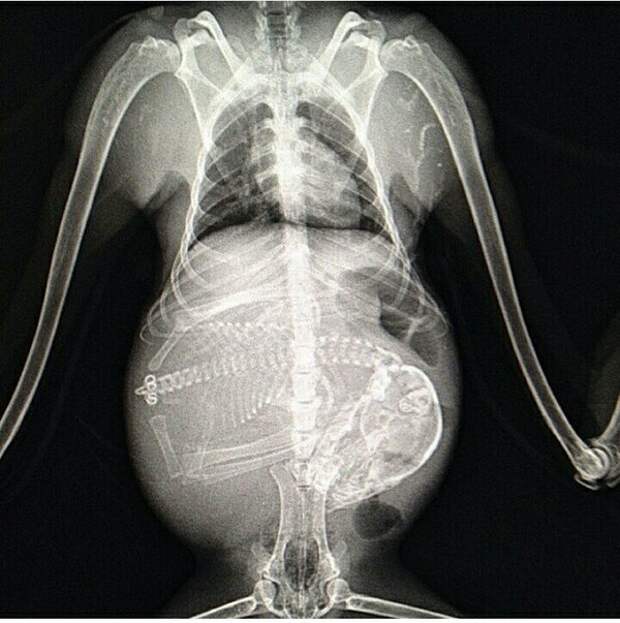

12. Беременная обезьяна